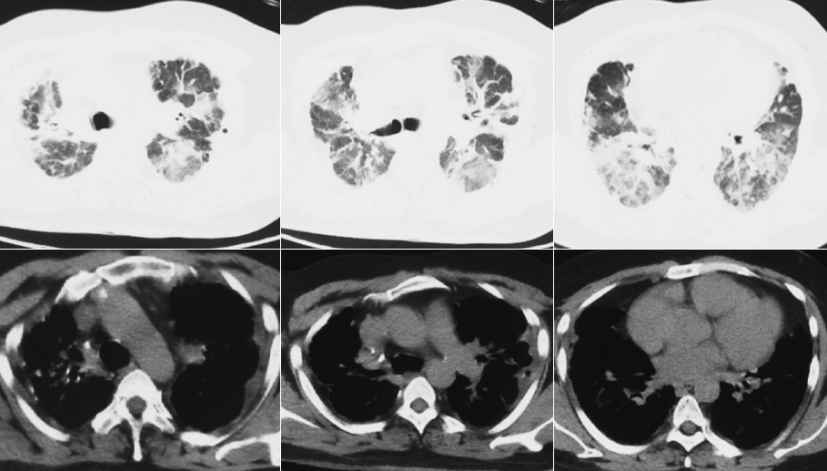

第1次住院(2018年1月8-21日):2018年1月,患者无明显诱因出现咳嗽、咳少量白痰,伴剧烈活动后气短,闻刺激性气味或冷空气咳嗽加重,于当地县医院住院。1月19日完善胸部CT,诊断为“急性支气管炎,支气管扩张”,于1月8-21日予哌拉西林他唑巴坦3.375 g qd+左氧氟沙星0.4 g qd抗感染治疗2周,症状减轻出院,仍间断咳嗽、剧烈活动后气短,冬季感冒后加重。1月19日胸部CT:双肺各叶散在分布斑片样高密度影,密度不均,边界模糊,双肺上叶病灶可见支气管充气征,双侧胸膜局限性增厚(图1)。

第2次住院(2020年10月30日-11月12日):2020年10月18日“着凉”后再次咳嗽、气短加重,伴少量白痰,伴右侧胸痛,慢走200 m感气短,重体力活时可自闻及喘鸣音。当地门诊给予“头孢哌酮他唑巴坦、左氧氟沙星”静滴抗感染12 d,效果差,再次于沧县医院住院。血常规:WBC 13.23×109/L(↑),NEU 10.65×109/L(↑),LYM 1.7×109/L,血红蛋白156 g/L,血小板491×109/L。血气分析(吸氧条件不详):pH 7.422,PaO2 66.5 mmHg(↓),PaCO2 46 mmHg(↑),HCO3- 29.9 mmol/L(↑),BE 5.4 mmol/L,Lac 2.1 mmol/L。血沉 6.6 mm/h。痰细菌培养结果为粪产碱杆菌。超声心动图:左房内径31 mm,左室内径42 mm,右房内径38 mm,右室内径36 mm,主肺动脉19 mm,射血分数(EF)56%。三尖瓣少量反流,左室舒张功能减低。10月30日胸部CT:右肺上叶支气管旁斑片影,较2018年1月19日增多,左上肺新发斑片影、结节影,双肺胸膜增厚,较前加重(图2)。

诊断为“肺炎,支气管扩张”,予抗感染治疗2周并加用甲强龙治疗(图3)。咳嗽、喘息明显减轻出院,继续口服醋酸泼尼松15 mg qd(11月13日-12月7日,24 d)。

11月10日(激素治疗12 d)复查胸部CT:双肺斑片影、结节影、磨玻璃影较前吸收(图4)。